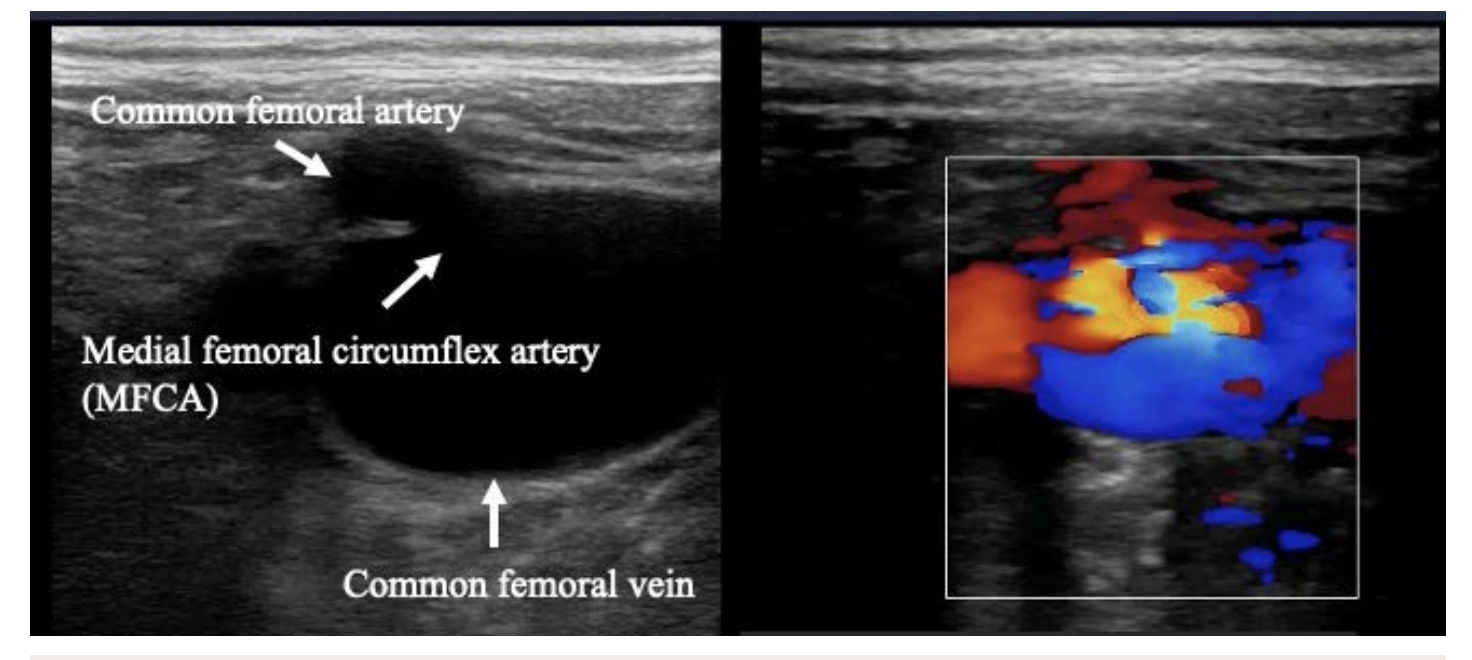

This patient was a 67-year-old woman who had been caught in a cultivator and had her right leg amputated in the 1980s. She had no medical history of congestive heart failure or shortness of breath. She was administered direct oral coagulant, a β-blocker, and a proton pump inhibitor because of chronic atrial fibrillation. Twenty-seven years after the accident, she presented to our hospital because of a swollen left leg and shortness of breath. Her blood pressure was 125/82 mmHg, heart rate was 100/min with atrial fibrillation, and saturation was 95% in room air. The results of a complete blood test as well as renal, liver, and thyroid function tests were all normal but the serum BNP level rose to 607.1 pg/mL. Chest radiography confirmed cardiac dilation, pulmonary congestion, and pleural effusion (Figure 1). She was given 20 mg/day furosemide to treat congestive heart failure. We confirmed a bruit at her left groin and pulsations in a lower leg vein. Transthoracic echo cardiography (TTE) showed an ejection fraction of 55%, her right ventricular pressure increased to 44 mmHg, and severe tricuspid valve regurgitation was detected. Vascular echo showed an arteriovenous fistula (AVF), shunt flow, and an expanded femoral vein (Figure 2). A computed tomography (CT) angiography was performed and revealed a left medial femoral circumflex artery (MFCA)–left common femoral vein (CFV) fistula (Figure 3).